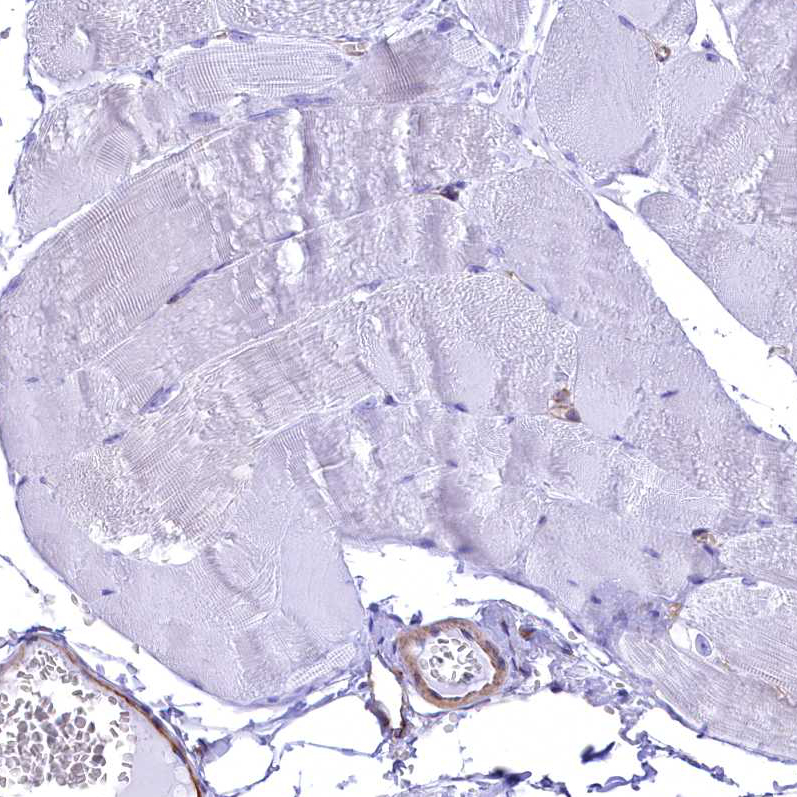

Immunohistochemistry analysis in human lymph node and skeletal muscle tissues using HPA042564 antibody. Corresponding SEPT9 RNA-seq data are presented for the same tissues.